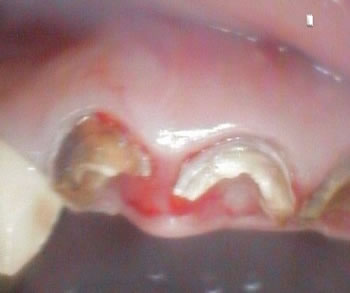

引き出すためのフックを装着しました。

1眼レフではなくて、簡易的な口腔内カメラだけに画像が粗い!

汗!